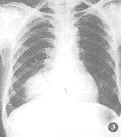

2.2.3 瘤体影像特征 X线表现呈球型10例(左肺4例,右肺6例);团块状20例(左肺6例,右肺14例)。球型的X线特征是:肿块大多呈圆形,椭圆形,大小1~4 cm不等,边缘光滑,密度均匀,轮廓清楚(图1)肿块周围多有假性包膜。团块型的特征是:病灶大小形态不一,密度多不均匀,边缘模糊,境界不清,有的形似大片渗出的炎性阴影(图2,3)或在肿块周围形成“外套”性炎症。4例可见明显的长毛刺,6例体层片上显示肿块内侧缘与肺门之间牵拉的索条影,2例形成压迫性肺不张,1例瘤体形似“倒雪人”状(图4)。

图2 右上肺见肿块呈大片团块影,并见肿块内侧缘与肺门之间呈牵拉的索条影,病理证实肺炎性假瘤

3.3 影像学表现:肺炎性假瘤可发生在两肺的任何部位,本组右上肺(12/20)多于左上肺(2/10)。位于下叶的假瘤多位于下叶背段和内后基底段。球型瘤体一般边缘光滑锐利,直径多在1~4 cm,密度比较均匀,周围肺野清晰。团块样的瘤体一般境界不清,边缘模糊,部分病灶密度浓淡不匀,如多次并发急性炎症,可造成“瘤”影扩大,在其周围恰似炎性浸润的片状影。因此,假瘤边缘清楚与否取决于肿块周围的病理变化,境界面清楚者瘤体周围一般有假性包膜。若病灶处于急性阶段时,假瘤周围显示炎性渗出,在瘤体周围多呈模糊影,亦无假包膜形成。本组1例呈“堆雪人”状,这是由于假瘤生长不规则所致。3例假瘤跨叶生长的原因,可能是跨叶浸润的炎症使得假瘤跨叶融合的结果[1,4]。